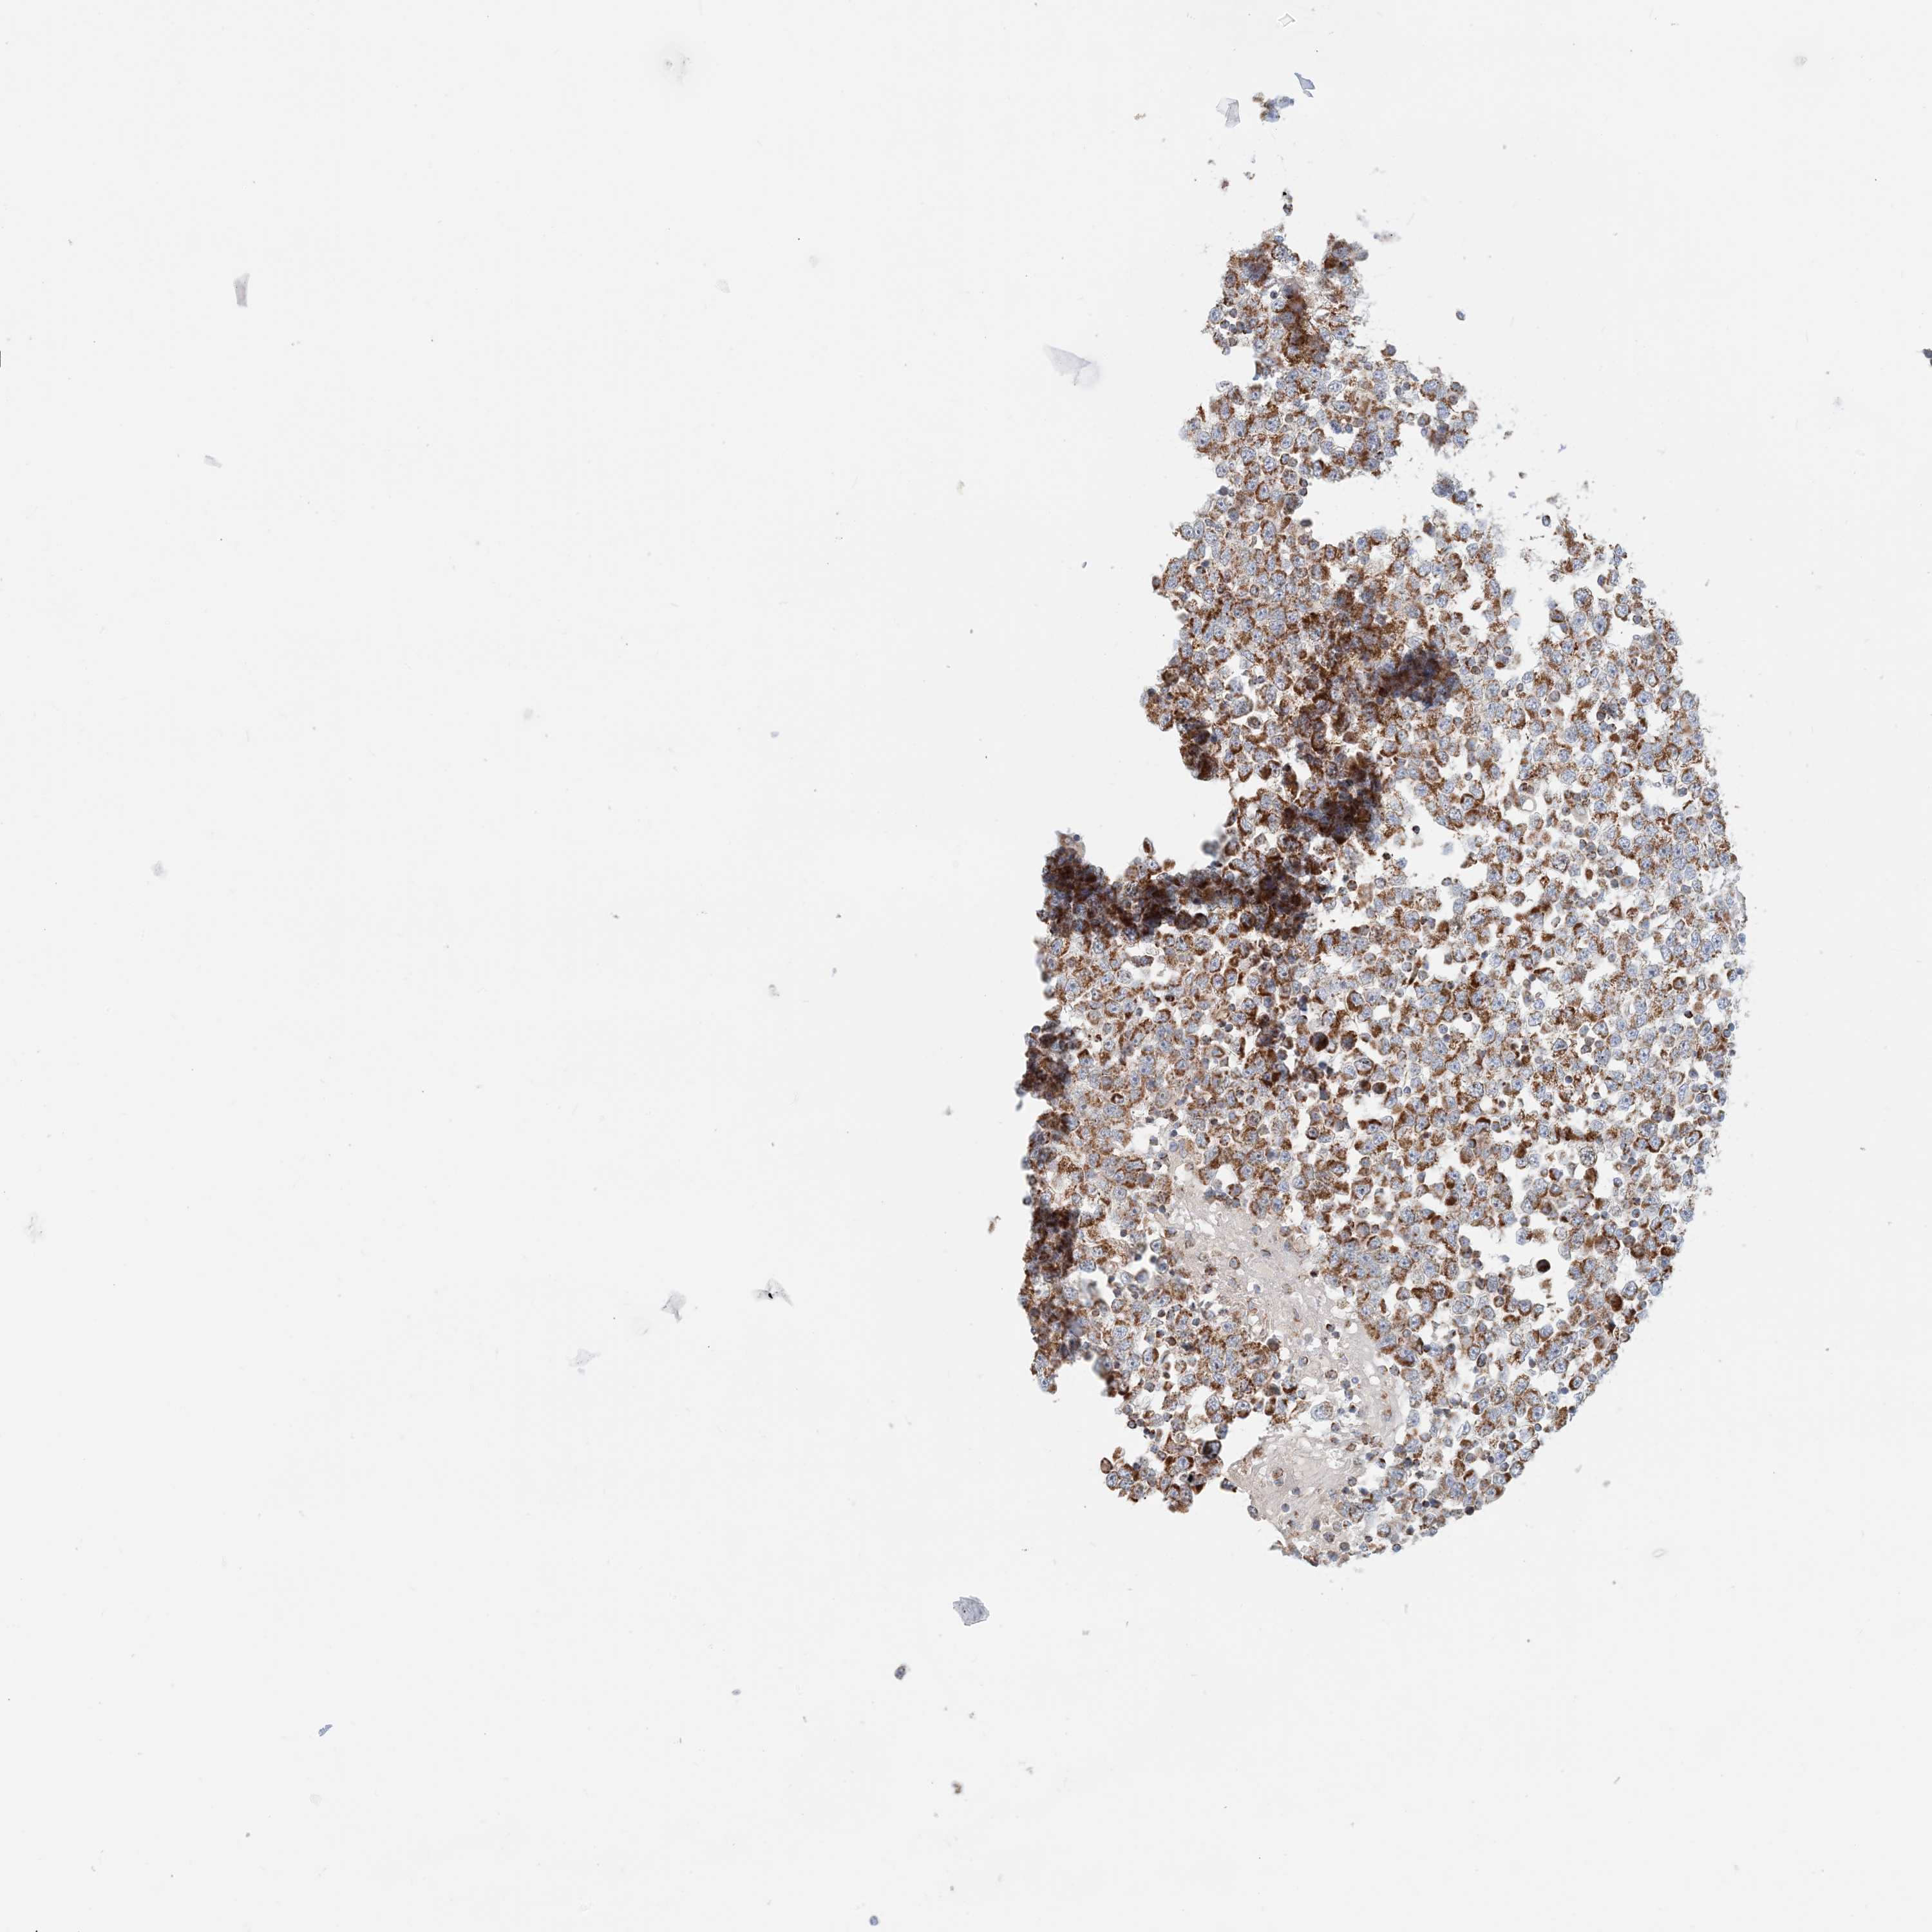

TESTIS CANCER - Protein expressioni

A mouse-over function shows sample information and annotation data. Click on an image to view it in a full screen mode. Samples can be filtered based on level of antibody staining by selecting one or several of the following categories: high, medium, low and not detected. The assay and annotation is described here.

Note that samples used for immunohistochemistry by the Human Protein Atlas do not correspond to samples in the TCGA dataset.

Antibody stainingi

Antibody staining in the annotated cell types in the current human tissue is reported as not detected, low, medium, or high, based on conventional immunohistochemistry profiling in selected tissues. This score is based on the combination of the staining intensity and fraction of stained cells.

Each image is clickable and will lead to virtual microscopy that enables deeper exploration of all samples and also displays staining intensity scores, fraction scores and subcellular localization as well as patient and tissue information for each sample.

Antibody HPA031966

Staining

High

Medium

Low

Not detected

Intensity

Strong

Moderate

Weak

Negative

Quantity

>75%

75%-25%

<25%

None

Location

Nuclear

Cytoplasmic/membranous

Cytoplasmic/membranous,nuclear

Carcinoma, Embryonal, NOS

Seminoma, NOS